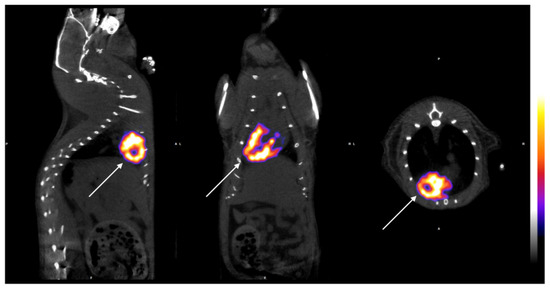

3.1. SPECT-CT Evaluation

| RATIO LV/RV (−7d) | 8.72 ± 0.36 | 8.77 ± 0.20 | 8.86 ± 0.22 | 0.480 |

| RATIO LV/RV (7d) | 8.69 ± 0.37 | 7.50 ± 0.24 * | 7.50 ± 0.29 * | <0.005 |

| RATIO LV/RV (14d) | 8.71 ± 0.34 | 7.59 ± 0.28 * | 8.00 ± 0.27 *,† | <0.005 |